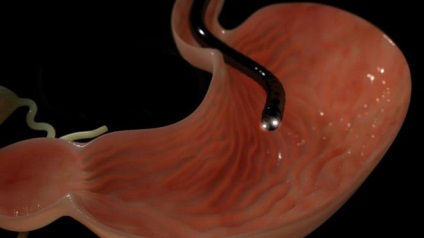

Abban a pillanatban, aktívan fejlesztett technikák, amelyek lehetővé teszik, hogy érzékeli az onkológiai másik koncepció fázisban. Erre a célra speciális tumormarkerek, amelyek lehetővé teszik számunkra, hogy meghatározza a páciens vérének összetételét. Ezen túlmenően azt is hozzá kell rendelni a gyomortükrözés.